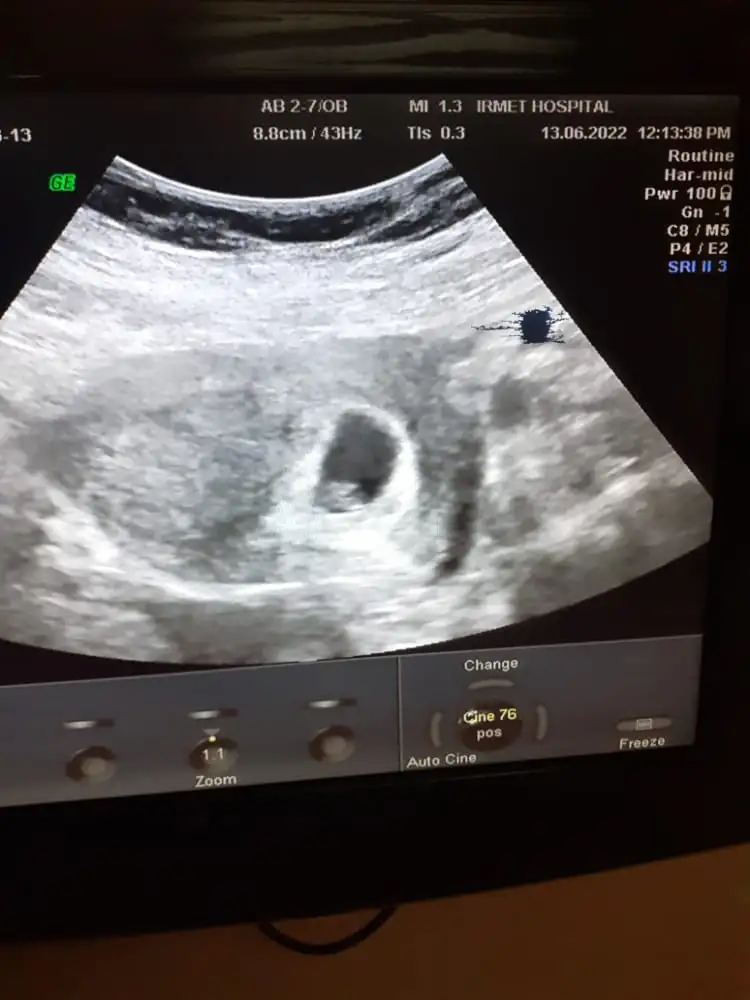

Bizim bebeğimiz içinde tahminde bulunabilir misin :) görüntüler karından

çok ortada, başka görüntü var mı?Merhaba satA göre 7+2 ultrasona göre 6+4 karından ultrason banada bir tahminde bulunur musunuz

kese oluşmuş bebek henüz göremedim tahmin yapılamaz6 haftalığız karından bakildi birde bize bir tahminde bulunur musunz